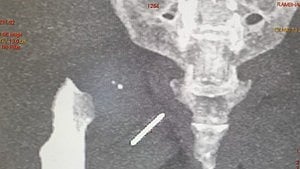

ഇടുപ്പിൽ സൂചി തറഞ്ഞിരുന്നത് മൂന്നു വർഷം; അപൂർവ ശസ്ത്രക്രിയയിലൂടെ പുറത്തെടുത്തു

ന്യൂഡല്‍ഹി: 49 കാരിയുടെ ഇടുപ്പിന്റെ പേശികളില്‍ മൂന്ന് വര്‍ഷമായി തറഞ്ഞിരുന്ന സൂചി ശസ്ത്രക്രിയയിലൂടെ പുറത്തെടുത്തു. തയ്യലിനിടെയാണ് സൂചി ഇടുപ്പില്‍ തറഞ്ഞ് കയറിയത്. സൂചി തറഞ്ഞ് കയറിയത് അറിയാതിരുന്ന രംഭാ ദേവിക്ക് സ്ഥിരമായി ഇടുപ്പ് വേദനയുണ്ടായിരുന്നു. വേദന വര്‍ഷം കഴിയുന്തോറും അസഹനീയമാവുകയും തുടര്‍ന്ന് നടത്തിയ വിശദമായ പരിശോധനകളെത്തുടര്‍ന്നാണ് സൂചി കണ്ടെത്തിയത്.

തയ്യലിനിടെ ഓര്‍മിക്കാതെ കട്ടിലില്‍ സൂചി വെച്ച് മറന്നു. മറ്റെന്തോ എടുക്കാന്‍ വേണ്ടി എഴുന്നേറ്റപ്പോള്‍ കാല്‍ വഴുതി കട്ടിലിലേക്ക് വീണു. നല്ല വേദനയുണ്ടായെങ്കിലും സൂചി കുത്തിക്കയറിയതാണെന്ന് മനസിലായില്ല. ഒടിഞ്ഞ ബാക്കി ഭാഗം കട്ടിലില്‍ നിന്ന് കണ്ടെത്തുകയും ചെയ്തു. സൂചിയുടെ ബാക്കി ഭാഗം റൂമിലാണെന്ന് കരുതി നോക്കിയെങ്കിലും കണ്ടെത്താനായില്ല. അതേസമയം, വേദനയുണ്ടായത് വീണതിന്റേതാണെന്നാണ് കരുതിയത്. നാളുകള്‍ കഴിയുമ്പോഴേക്കും വേദന അസഹനീയമായി വര്‍ധിച്ചു വന്നു. ഇതേത്തുടര്‍ന്നാണ് ഡോക്ടറെ കാണിക്കാന്‍ തീരുമാനിച്ചത്. എക്‌സ് റേ എടുത്തപ്പോഴാണ് ഇടുപ്പില്‍ സൂചി കുടുങ്ങിയത് കണ്ടത്.

പിന്നീട് ശസ്ത്രക്രിയ ചെയ്യാന്‍ നോക്കുമ്പോള്‍ പല ഡോക്ടര്‍മാരും തയ്യാറായില്ല. ശസ്ത്രക്രിയ അതിസങ്കീര്‍ണമാകുമെന്നതിനാലാണ് ഡോക്ടര്‍മാര്‍ നിരസിക്കാന്‍ കാരണം. ശസ്ത്രക്രിയ വിജയകരമാണെന്നും രംഭാ ദേവി സുഖമായിരിക്കുന്നുവെന്നും ഡോക്ടര്‍മാര്‍ പറഞ്ഞു.

എക്‌സ് റേ എടുത്തപ്പോഴാണ് ഇടുപ്പില്‍ സൂചി കുടുങ്ങിയത് കണ്ടത്.

വേദന വര്‍ഷം കഴിയുന്തോറും അസഹനീയമാവുകയും തുടര്‍ന്ന് നടത്തിയ വിശദമായ പരിശോധനകളെത്തുടര്‍ന്നാണ് സൂചി കണ്ടെത്തിയത്.  എക്സ്റേ, ഐഎഎന്‍എസ്